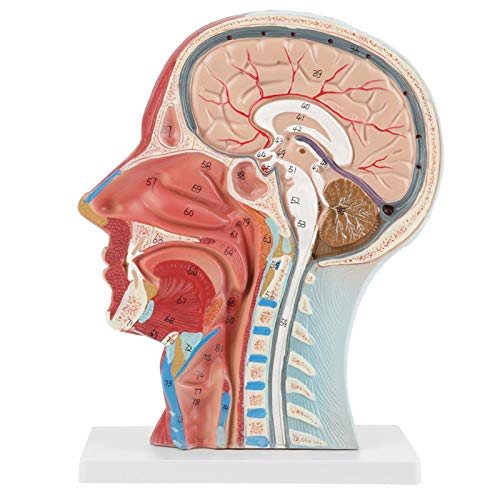

voor scholen, ziekenhuis, lichamelijke gezondheid onderwijs, anatomisch hoofd model, onderwijs tool keel anatomie…

Zeer gedetailleerde getallen gemarkeerd, verdiepen het begrip van de structuur van het menselijk brein, vasculaire structuren

De ene kant toont interne structuur, de andere toont spier- en vasculaire structuur

Toepasbaar op scholen, ziekenhuis, lichamelijke gezondheidsonderwijs, kan worden gebruikt als een onderwijsinstrument

De ene kant is voorzien van interne anatomie, de andere toont spier- en vasculaire anatomie. Zeer gedetailleerde getallen gemarkeerd, verdiepen het begrip van de structuur van de menselijke hersenen, vasculaire structuren. De gehele structuur is stevig gemonteerd op een kunststof basis, gemakkelijk te observeren. Het model is gemaakt van PVC-kunststof, dat corrosiebestendig, licht is en een hoge sterkte heeft. Toepasbaar op scholen, ziekenhuis, lichamelijke gezondheidsonderwijs, kan als leerhulpmiddel worden gebruikt.

Zeer gedetailleerde getallen gemarkeerd, verdiepen het begrip van de structuur van het menselijk brein, vasculaire structuren

De ene kant toont interne structuur, de andere toont spier- en vasculaire structuur

Toepasbaar op scholen, ziekenhuis, lichamelijke gezondheidsonderwijs, kan worden gebruikt als een onderwijsinstrument